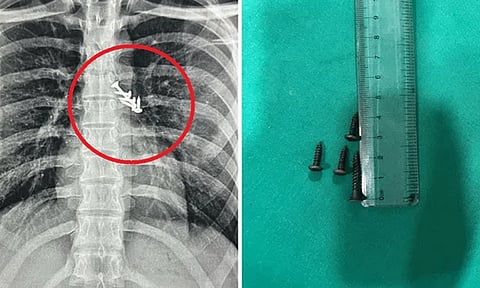

மகாராஷ்டிரா மாநிலம் பிம்பிரி மருத்துவமனையில், உறங்கிக்கொண்டிருந்த இளைஞர் தவறுதலாக விழுந்த ஆணிகளை விழுங்கிவிட்டதாக கூறி சிகிச்சைக்கு அனுமதி செய்யப்பட்டார். மருத்துவர்கள் ஸ்கேன் செய்தபோது நுரையீரல் மற்றும் வயிறு பகுதியில் ஆணிகள் இருந்தது.

உடனடியாக சுமார் 3 மணிநேர அறுவை சிகிச்சை செய்யப்பட்டு ஆணிகள் வெளியே எடுக்கப்பட்டன. இதனால் 19 வயது இளைஞரின் உயிர் காப்பாற்றப்பட்டது. மருத்துவ குழுவினருக்கு இளைஞரின் பெற்றோர் நன்றியை தெரிவித்துக்கொண்டனர்.